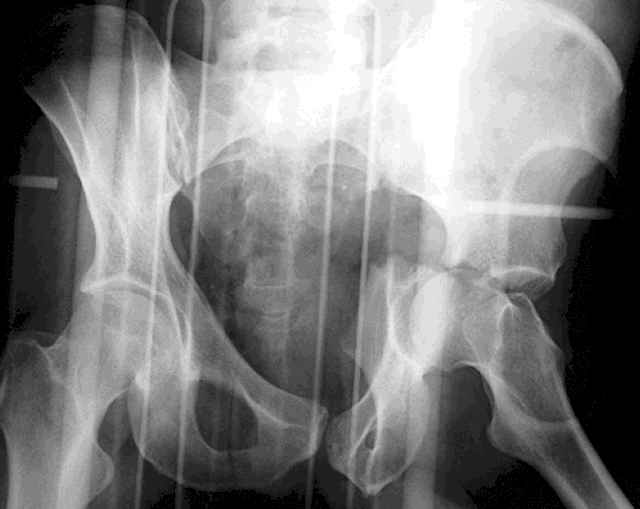

For Alex... here are some cannulated and 7mm screws for you... notice the fracture malreduction as indicated by the head subluxation on both views...this was a percutaneous technique without open reduction... I don¹t like it but there it is... the fixation technique is not at fault, because there was no open reduction of the fracture... but let¹s not get in to all that.